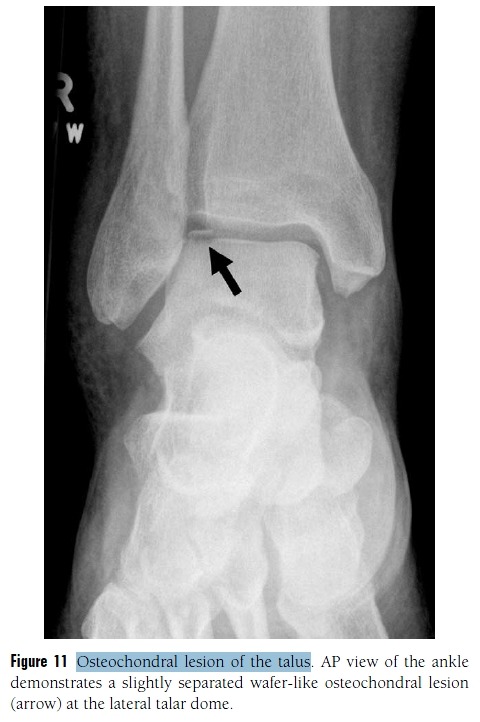

Figure 5 Fractures associated with ankle sprain. Avulsion fractures, particularly at the lateral malleolus, are common in the

setting of ankle sprain. Occasionally overlooked are sites of other fractures, including the following.

(D) Lateral talar process fracture. A fracture of the lateral talar process (arrow), also called a “snowboarder’s fracture,” is seen on this AP view of the ankle. These fractures are commonly missed and can be a source of chronic pain after a severe ankle sprain.